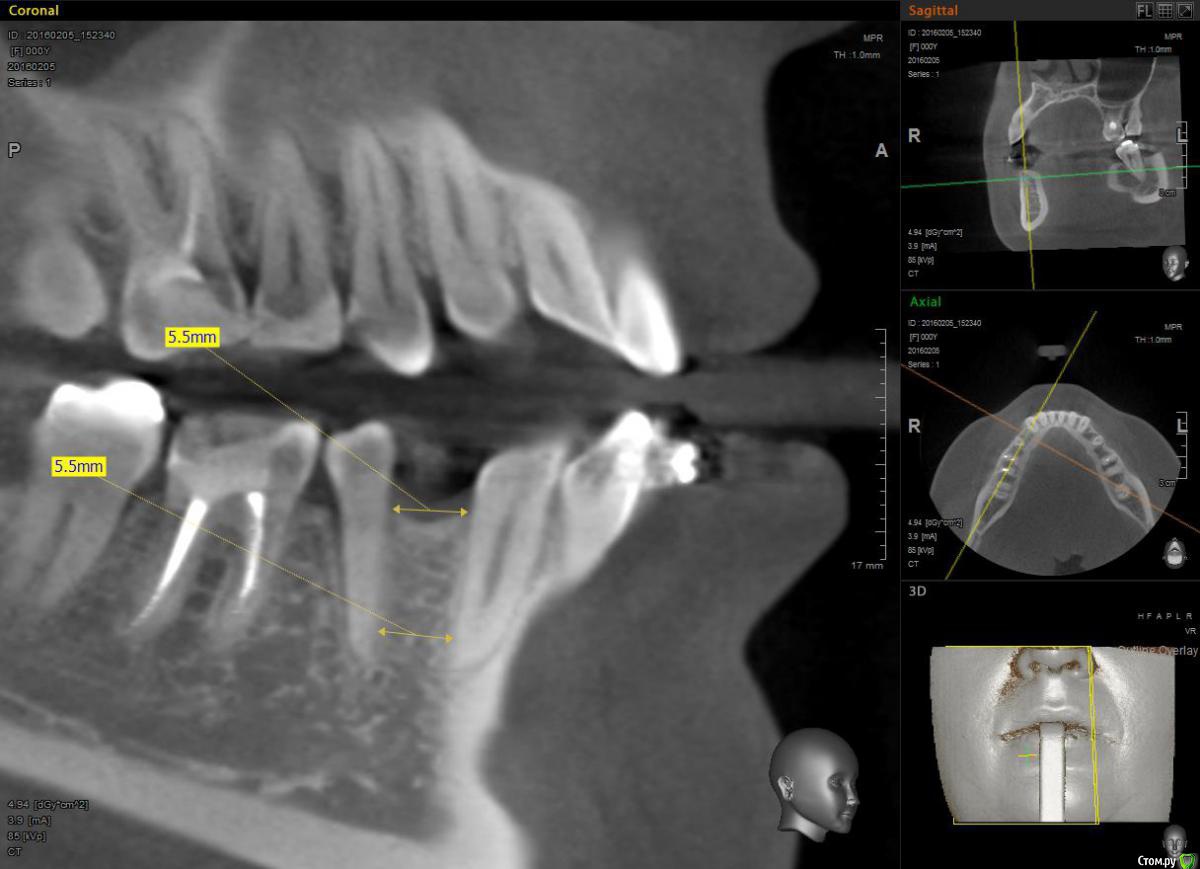

Janila Опубликовано 17 февраля, 2016 Поделиться Опубликовано 17 февраля, 2016 Прошу совет. Планирую установку имплантов на место не выросших нижних 4к. Стоят брейкеты. Имплантолог увидев снимки сказал места еще мало, и нужно сместить корни пятерок в параллель с шестерками. Иначе импланты погубят соседние зубы.Ортодонт сказал, что сдвинуть корни не возможно. Места мало, только под 3мм системы. Что делать, кому верить.Вариант с установкой мостов не рассматриваю. Ссылка на комментарий

Janila Опубликовано 2 августа, 2017 Автор Поделиться Опубликовано 2 августа, 2017 (изменено) Отчитаюсь по итогам своих мытарств. Была еще у 2х ортодонтов, один сказал, что можно, но с данной системой не работает, второй, видимо не хотел связываться, и сказал, что лечение обойдется в 30 тыс. (с уже установленной системой).Имплантацию сделали в августе 2016 года. Сейчас считаю, что поспешно, под давлением ортодонта. Были у меня нарекания к положению нижних 1-2-3х и 5х зубов, но он уверил, что все доведем до ума после имплантации. Ладно, импланты прижились, дело шло к установке коронок, но передние зубы все не вставали, а 5ки и 6ки не могли поделить место. То 6ки заваливались во внутрь к языку, то 5ки выпадали наружу. Так длилось 4 месяца и 3и активаций. Топтание надоело, мысли о некомпетентности ортодонта вновь стали посещать. И в предновогодние дни попала по рекомендации к детскому ортодонту, заведующей отделением в детской поликлинике. Первое, что никто не замечал, это были мои переростки - 8ки верхние, которые блокировали нижний ряд! После их удаления и свободной фиксации зубов на дуге (каждый зуб отдельно, а не цепочкой), все зубки встали по местам. Благодаря ее опыту, было все доведено до ума за 3 месяца и 2 активации, но конечно из-за поспешной имплантации, ортопеду пришлось коронки делать со смещенным центром. Стоят уже месяц и меня радуют. Так длинно не для специалистов, а для пациентов. Ищите и обрящите. Ортодонт должен быть с большим стажем если у вас сложный случай! На снимке после имплантации как раз видно, что 5ки "выпали" наружу, после их возвращения в зубной ряд, они стали прилегать в плотную к формирователям десны, при этом идеально совпали в позиции с верхним рядом. PS. Из предыстории - в принципе у меня не уродилось нижних 4ок и 8ок, а после беременности и рождения ребенка нижние передние зубы начали разъезжаться веером, хотелось остановить эти изменения из-за чего было начато это приключение. Изменено 2 августа, 2017 пользователем Janila Ссылка на комментарий